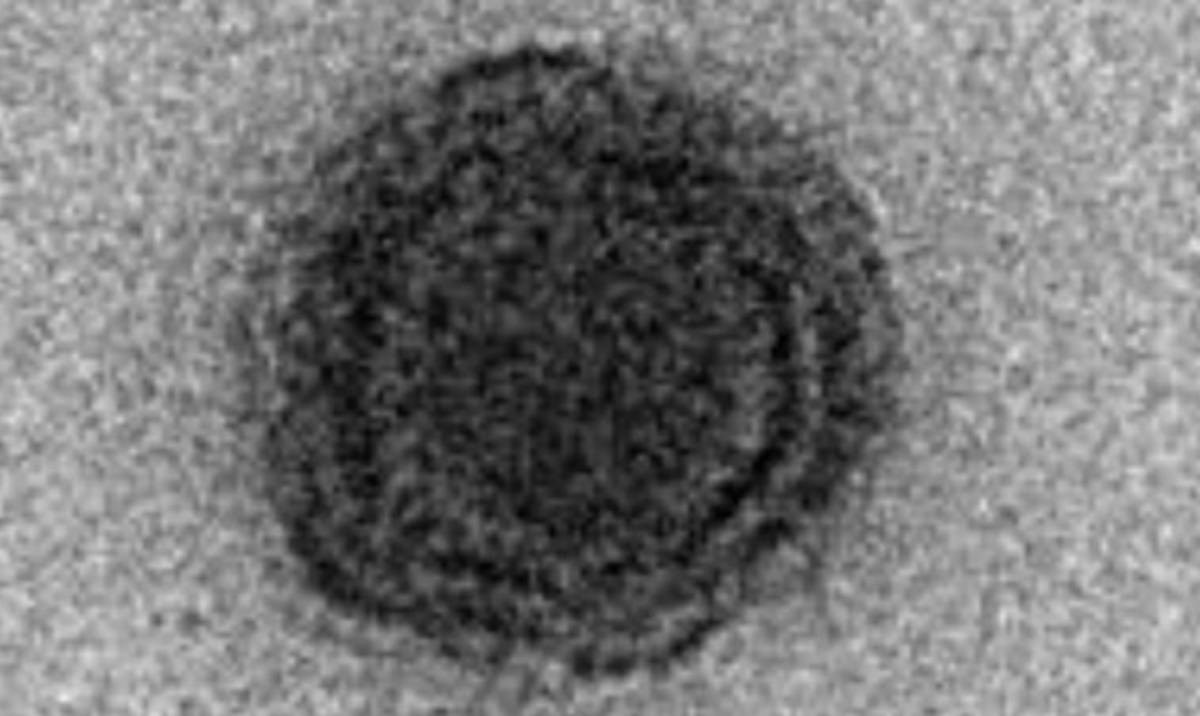

ZNANSTVENICI su nedavno otkrili novi, zagonetan virus čiji se genom čini potpuno nepoznat, odnosno sastoji se od gena koji nikad nisu dokumentirani u istraživanjima tog tipa.